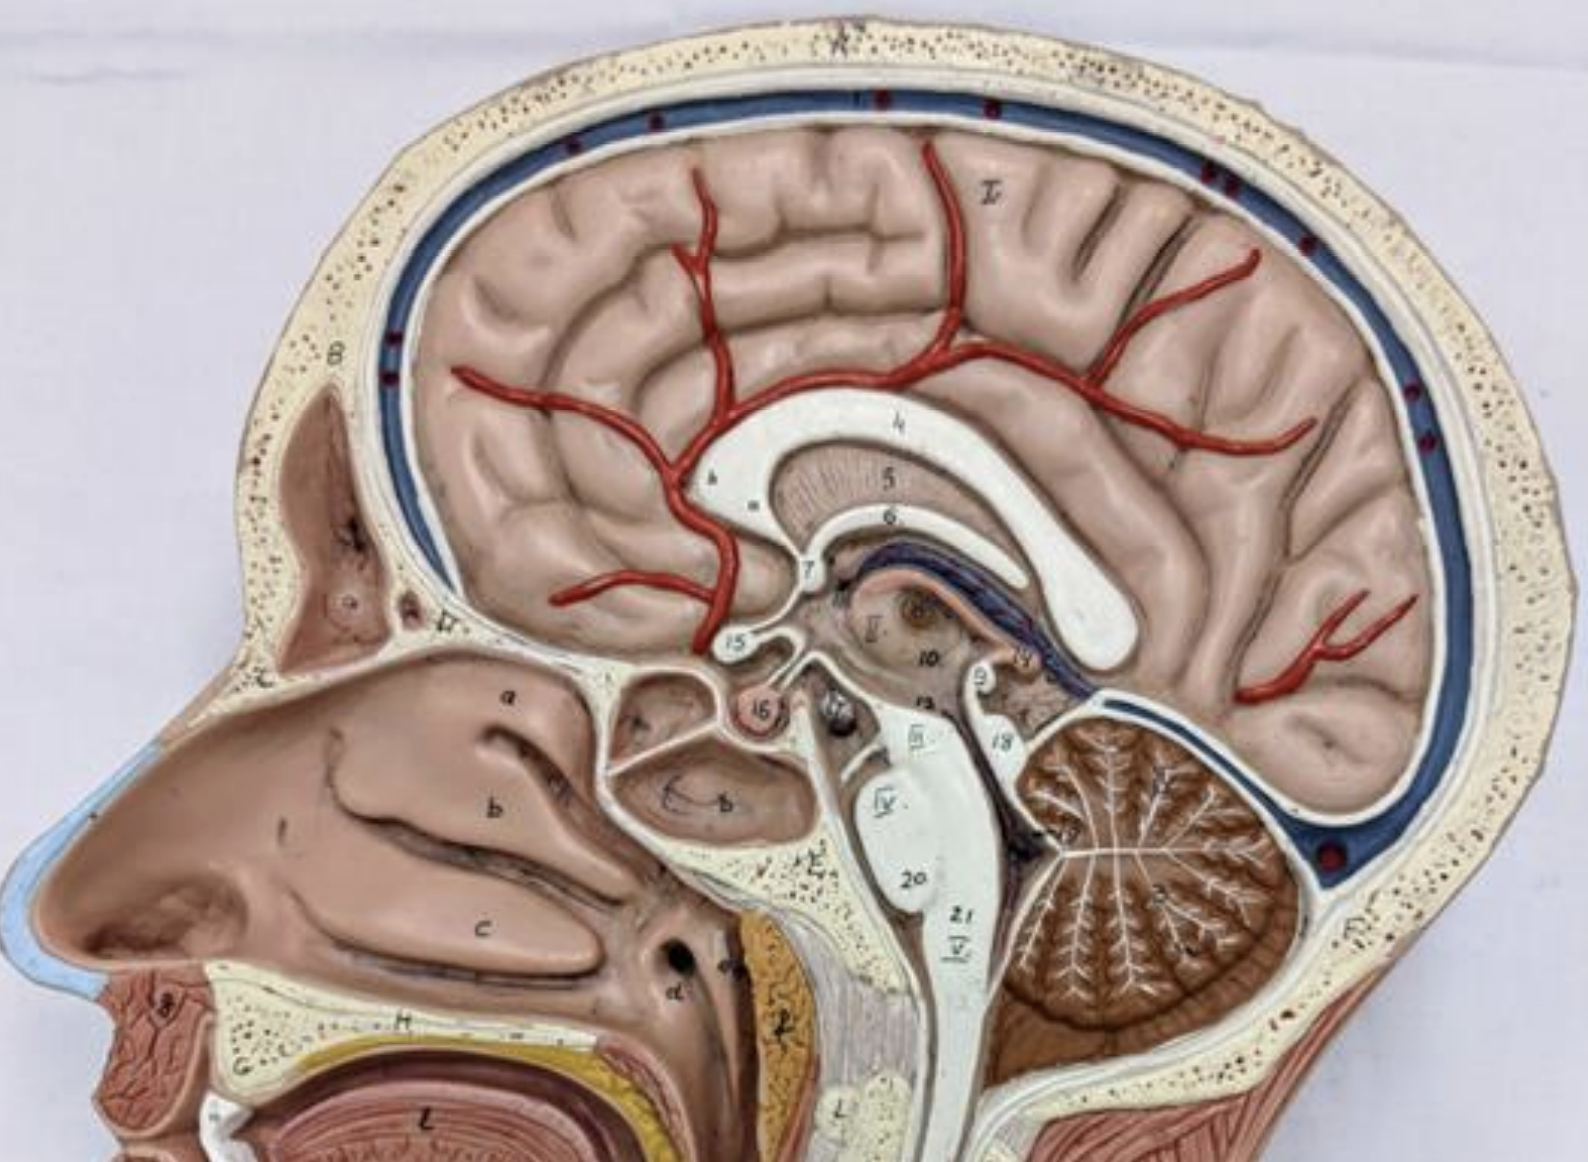

The lateral ventricle:

Anterior (frontal) horn

Body

Posterior (occipital) horn

Inferior (temporal) horn

Interventricular foramen

Foramen for the interthalamic mass

Third ventricle

Cerebral aqueduct

Fourth ventricle

Medial and lateral foramen

Central canal

Flow of CSF